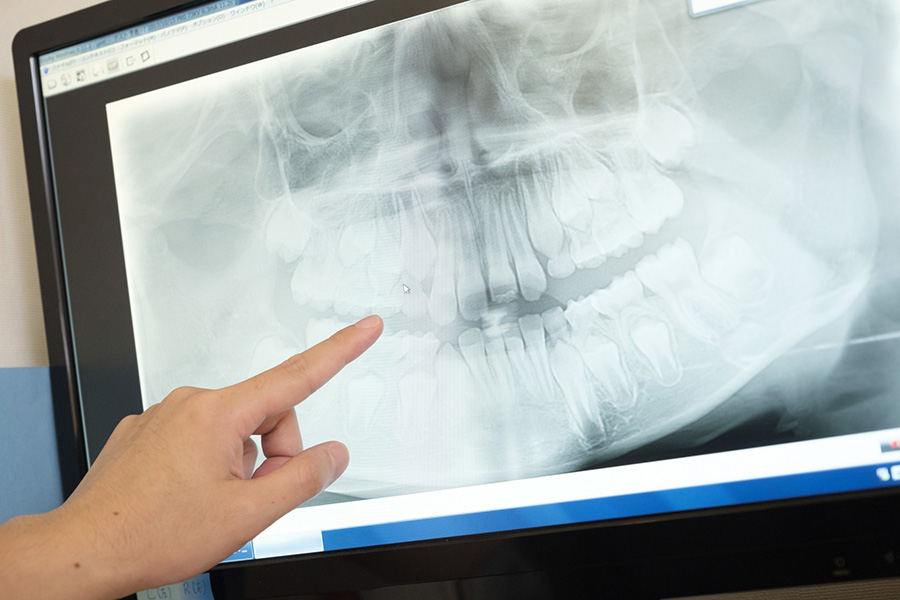

歯科用CTによる精密な診断

通常のレントゲンでは確認しにくい根管の形状や分岐、根の先の病変を、歯科用CTで立体的に把握します。見えない部分を正確に診断することで、治療の精度と成功率を高めます。